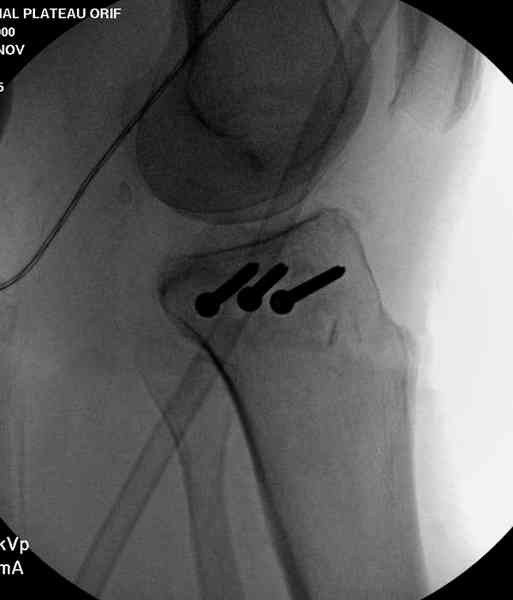

Из медиального окна можно приподнять латеральную

импрессию. Фиксация тремя параллельными шурупами в

эпифизарной части над импрессией. Создается крыша,

которая предупредит коллапс. На образовавшуюся полость - костная

пластика из аутокости или синтетический заменитель. Мы применяем

Osteoset в 4-5 мм диаметре таблеточки или иньекционную форму Prodens.